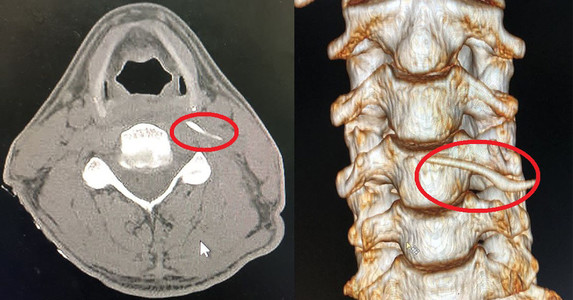

Uống ‘nước thần’ chữa hóc xương, người đàn ông nhập viện khẩn cấp

Y tế 24h -  18/12/2019

Cách đây gần 2 tuần, trong bữa cơm gia đình, anh Hoàng Văn Nam (SN 1978, trú huyện Quỳ Hợp, Nghệ An) bất ngờ bị hóc xương cá đồng.  Biết mình bị hóc...